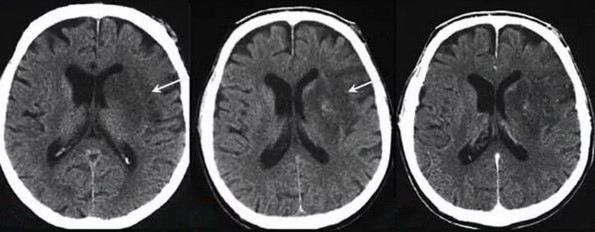

Иллюстрации и пояснения: гиподенсивный очаг на КТ головного мозга